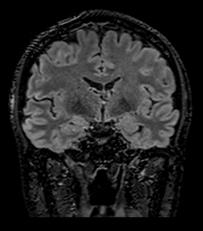

In particular DLR has an important clinical impact in anatomical regions that require a very high resolution, for example parts of the hippocampus and the claustrum.

“The DLR brings a spatial resolution that I have never seen before in neurologic imaging. I recently pointed out a brain area, for example the claustrum, that is almost invisible on standard MRI images even with very high resolution or high field devices. However, thanks

to the DLR we could highlight this kind of brain anatomy. So, indeed, there is a considerable advantage to using this technique.” Prof. Dousset said.

Prof. Tourdias worked at 7T to visualise extremely fine structures of the hippocampus while at Stanford. With DLR, he can now do this task with a 3T. “When we compared the images we realized that by pushing the 3T machine and processing with DLR that we were able to achieve a similar result to what we could achieve with 7T. I think this is the main surprise of the technology.” he said.

Atlas SPEEDER Head/Neck, T2, AiCE, Res: 0.2 x 0.2 x 2 mm, Scan time: 6:35 min.

Brain – Hippocampus

Brain Atlas SPEEDER Head/Neck, 3D FLAIR, AiCE, Res: 1 x 1 x 1.1 mm, Scan time: 4:55 min.